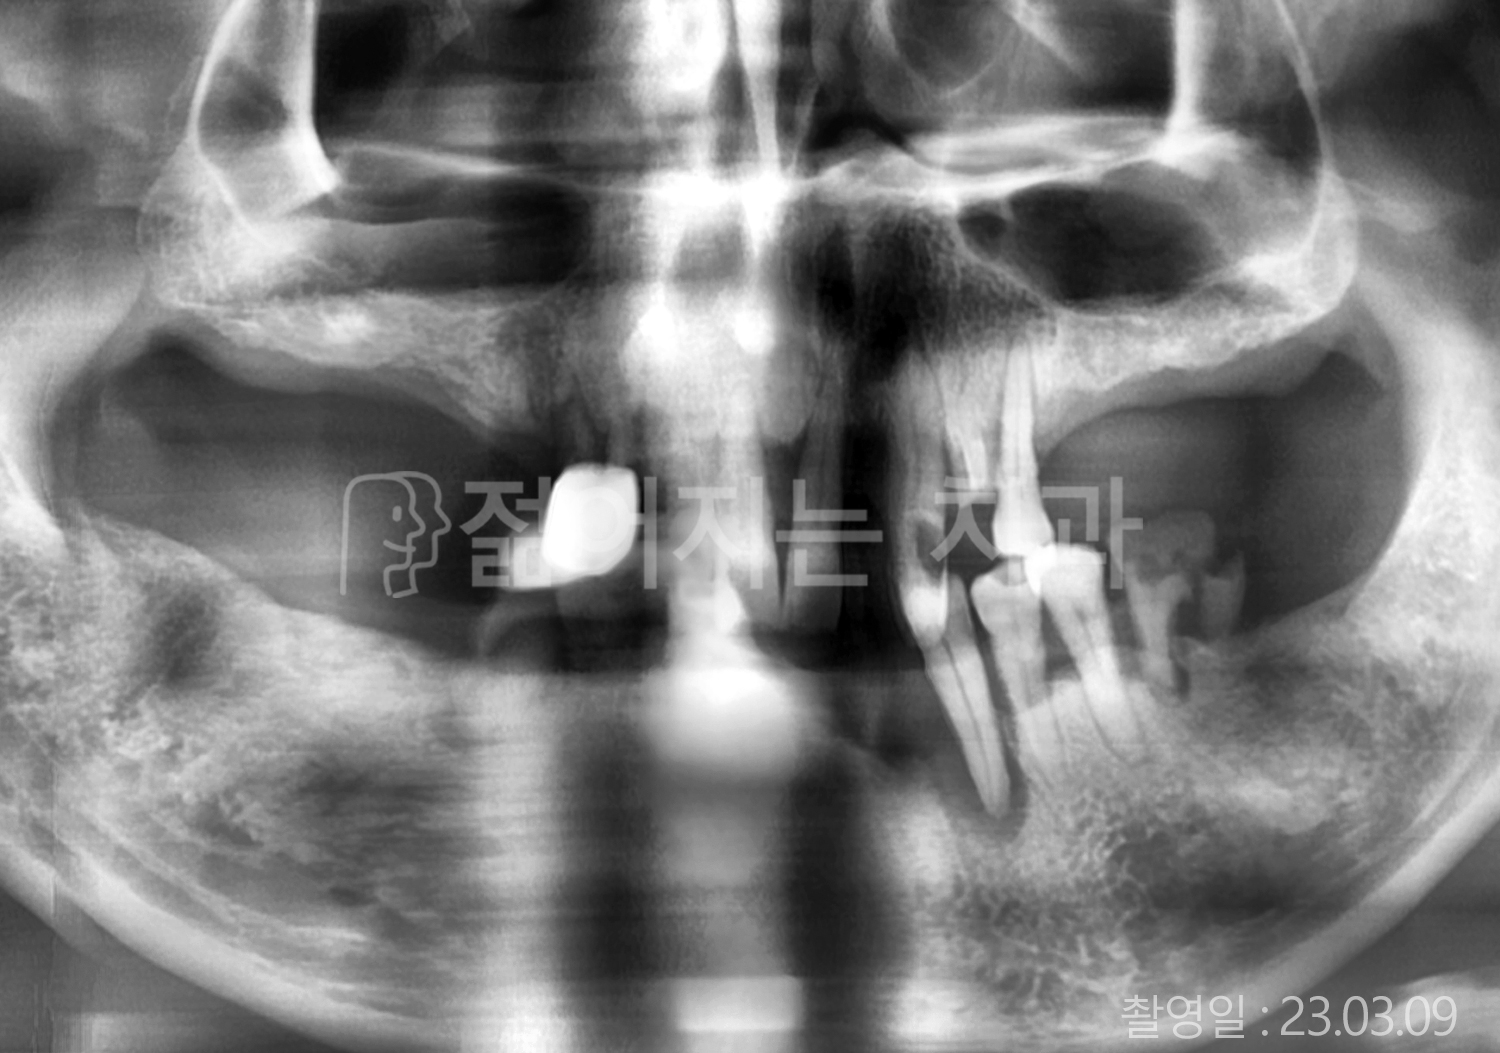

• 60대 전체치아 10개 이상 임플란트

• 50대 전체치아 10개 이상 임플란트

• 70대 고혈압, 암, 갑상선 질환 전체치아 10개 이상 임플란트

• 60대 고혈압, 당뇨, 고지혈증 전체치아 10개 이상 임플란트

• 40대 당뇨 전체치아 10개 이상 임플란트

• 70대 전체치아 10개 이상 임플란트

• 60대 당뇨 전체치아 10개 이상 임플란트

• 70대 고혈압, 당뇨 전체치아 10개 이상 임플란트